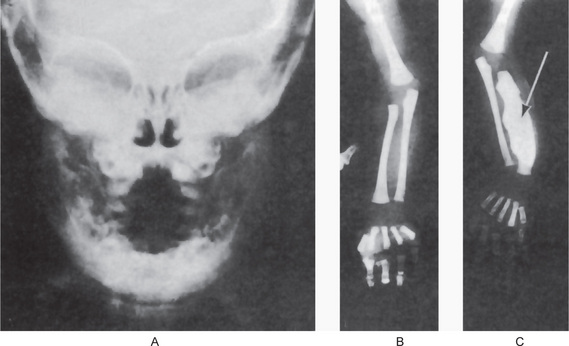

Radiographic examination reveals periosteal new bone formation that can be quite florid and subsequently becomes compact causing pronounced cortical thickening (Fig. 17-28). The periosteal new bone is seen in bones underlying areas of soft tissue swelling. The distribution is patchy and asymmetric but is multifocal, although cases of monostotic involvement have been reported. The mandible is almost invariably involved and other commonly affected areas include the clavicles, ribs and long bones of the limbs. Typically, the periosteal new bone or periosteal ‘cloaking’ is confined to the diaphyses of the long bones, sparing the metaphyses and epiphyses. There are a few reports of lytic areas affecting the skull vault and facial bones but this is uncommon. The spine, phalanges and pelvis are hardly ever involved. Increased uptake of radioisotope from a radioisotope bone scan shows areas of involvement before radiographic changes are present.

The maxilla exhibits progressive enlargement, the alveolar ridge becomes widened and the palate is flattened (Figs. 17-29, 17-30). If teeth are present, they may become loose and migrate, producing some spacing. When the mandible is involved, the findings are similar, but not usually as severe as in the maxilla. As the disease progresses, the mouth may remain open, exposing the teeth, because the lips are too small to cover the enlarged jaw.

Figure 17-29 Osteitis deformans.

There is diffuse enlargement of the maxilla and thickening of the dentulous (A) and edentulous (B) alveolar ridge. In addition, tipping of the teeth due to enlargement of the maxilla is obvious. (B, Courtesy of Dr Robert J Gorlin)

Figure 17-30 Paget’s disease.

Note the enlargement on the right maxilla. The patient was unable to use his denture.